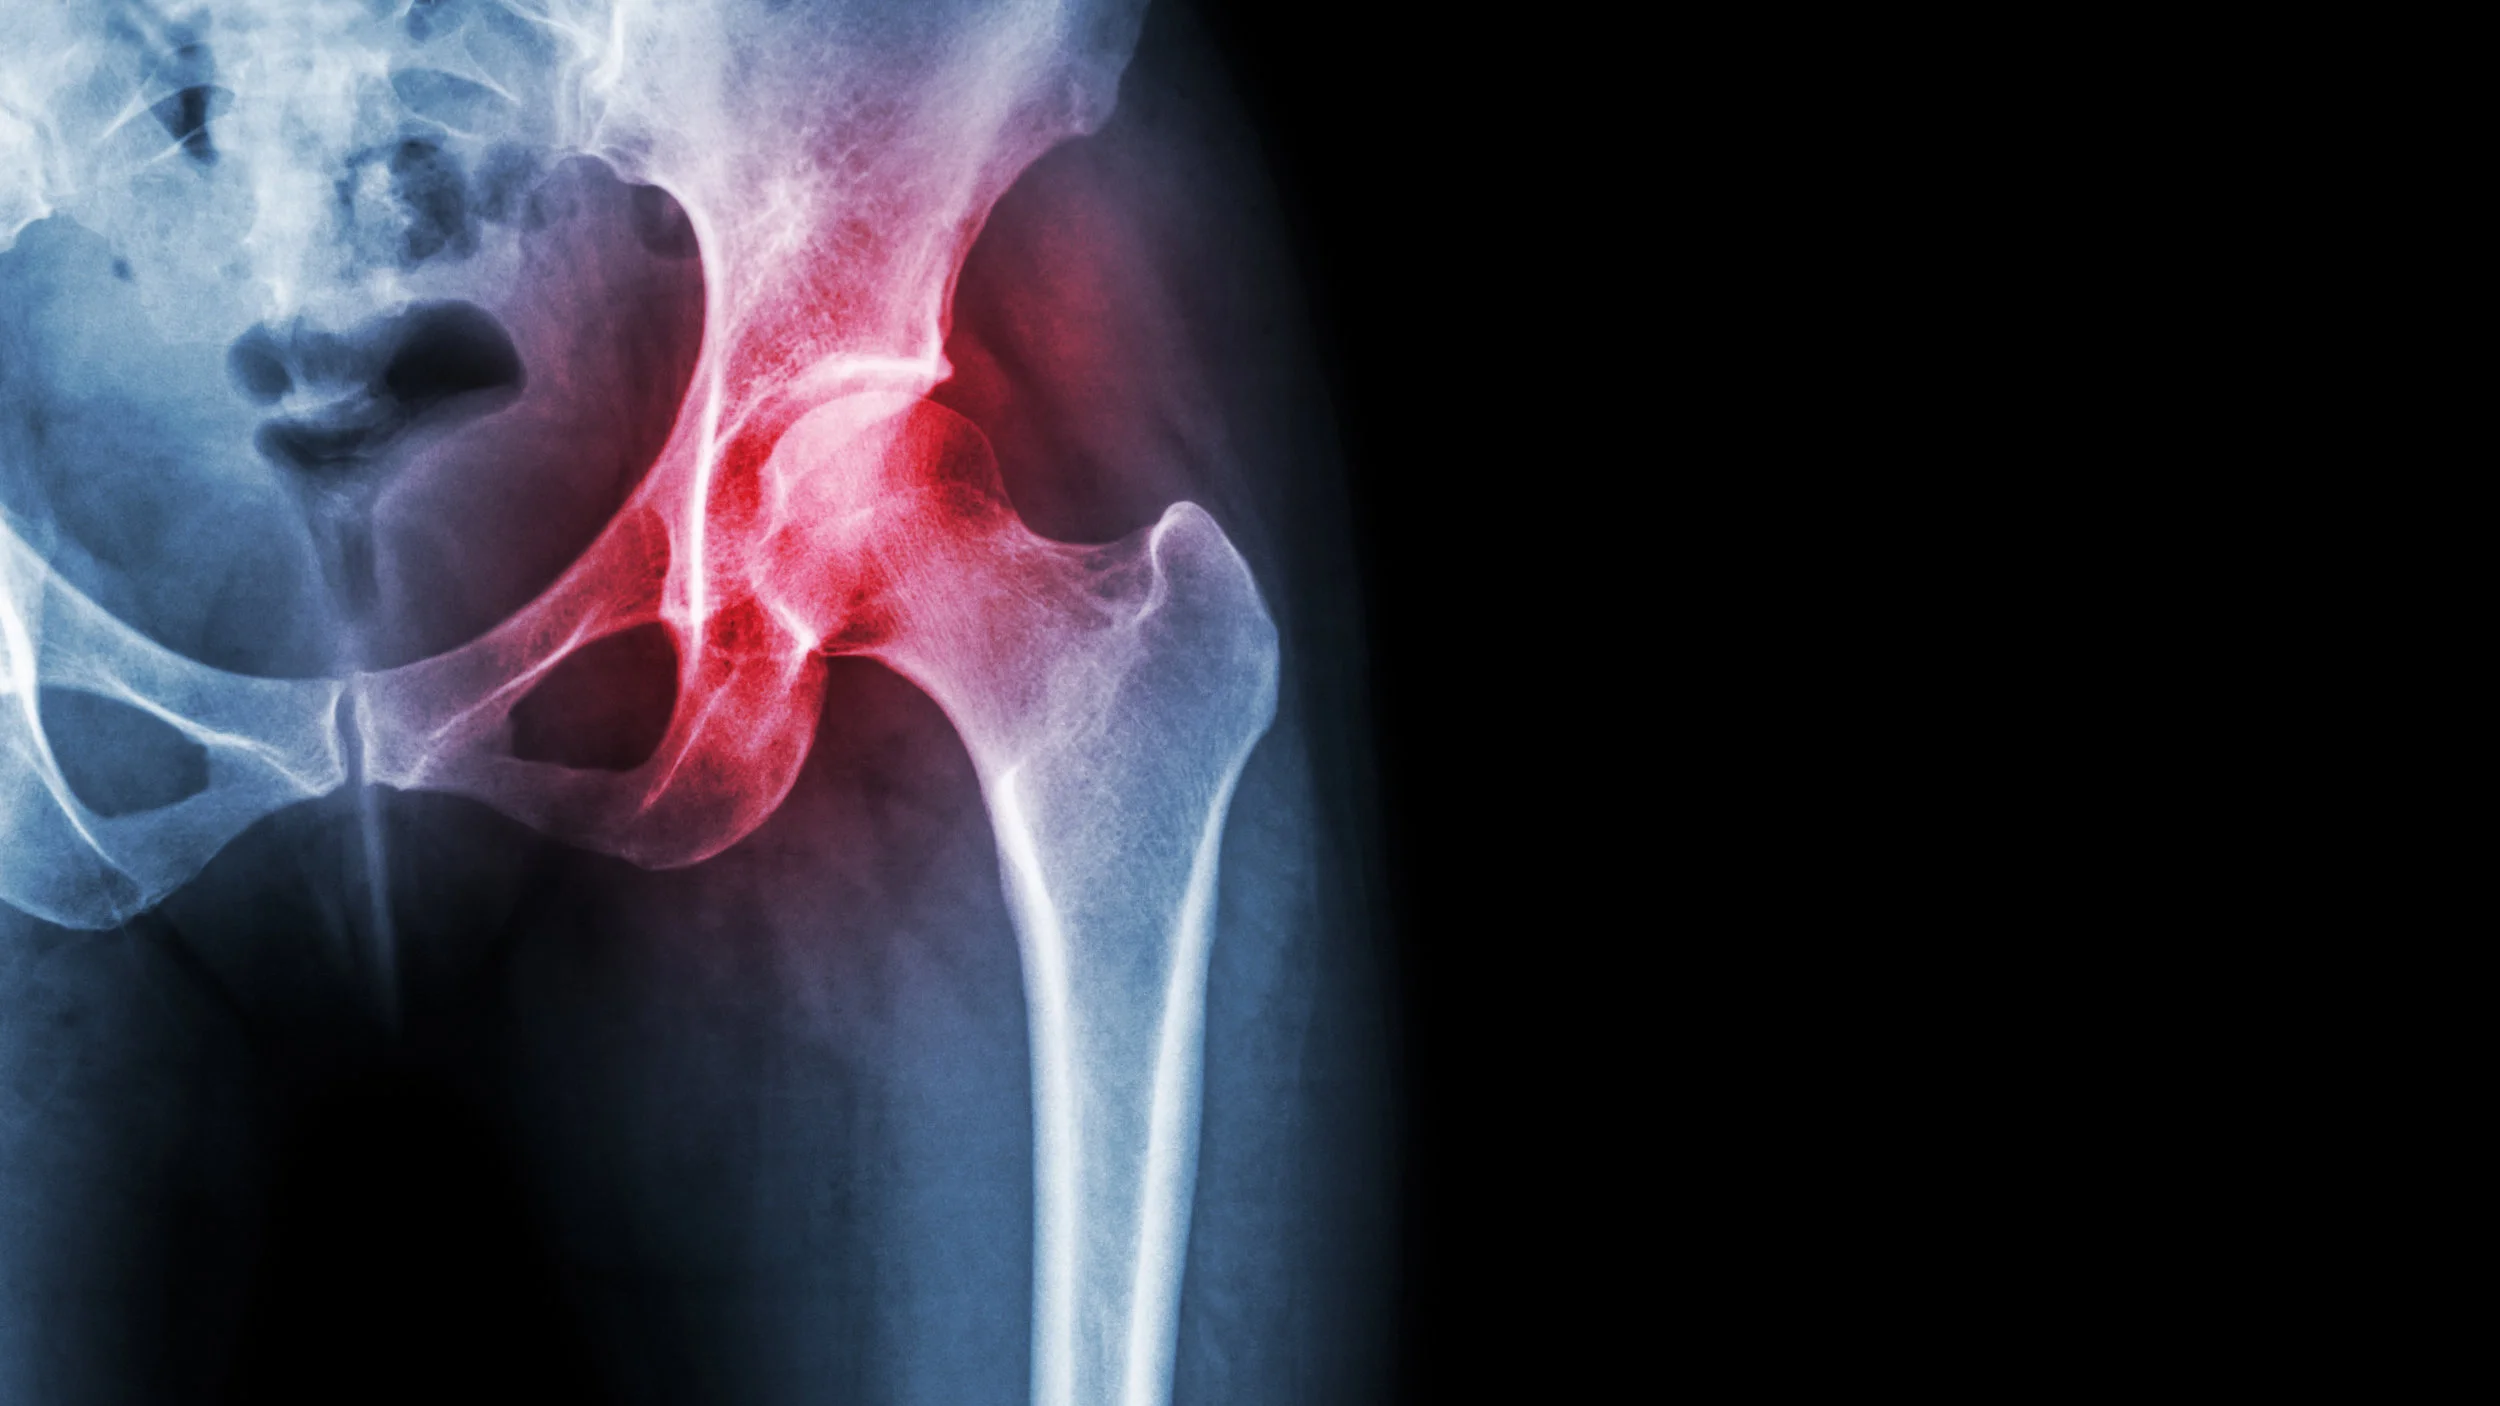

Artrose En Koud Weer. Alles over artrose heup symptomen, behandeling Zorg dus voor extra lagen kleding bij pijnlijke gewrichten Koud weer kan een zware tol eisen van iedereen, maar vooral van mensen met reuma

Veranderingen in het weer, zoals temperatuur, luchtvochtigheid en luchtdruk, worden vaak in verband gebracht met een verhoogd risico op lichamelijke aandoeningen. Toch vinden veel mensen dat koud en vochtig weer de pijn verergert In 20 procent van de gevallen vonden de onderzoekers kleine verschillen tussen de reacties van de patiënten op het weer, wat suggereert dat de ene patiënt juist meer pijn ervaart bij een lage luchtdruk en een andere patiënt bij een hoge luchtdruk.

5 tips om reumaklachten te voorkomen Paramedisch Centrum Twigt. Veranderingen in het weer, zoals temperatuur, luchtvochtigheid en luchtdruk, worden vaak in verband gebracht met een verhoogd risico op lichamelijke aandoeningen. Dit komt omdat de kou zorgt voor een slechtere doorbloeding van de spieren en de.